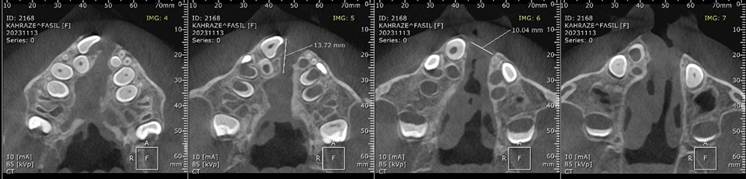

Cone-beam computed tomography (CBCT) localized palatal and alveolar clefts in the anterior and midline regions, documented rotation of tooth 11, absence of tooth 21, and a peg-shaped tooth 22. CBCT measurements revealed a nasal cleft width of 4.5 mm anteriorly and 8.9 mm posteriorly, a vomero-chondral deformity with anterior nasal spine (ANS) deformity, and an alveolar cleft width of 10.4 mm at the central incisor region and 17.5 mm in the canine-to-canine span (Figure 4).

Figure 4. Coronal Cone-Beam Computed Tomography (CBCT) Images Showing Palatal and Alveolar Clefts, Rotated Tooth 11, Absence of Tooth 21, and Measurements of Cleft Widths at the Nasal and Alveolar Regions